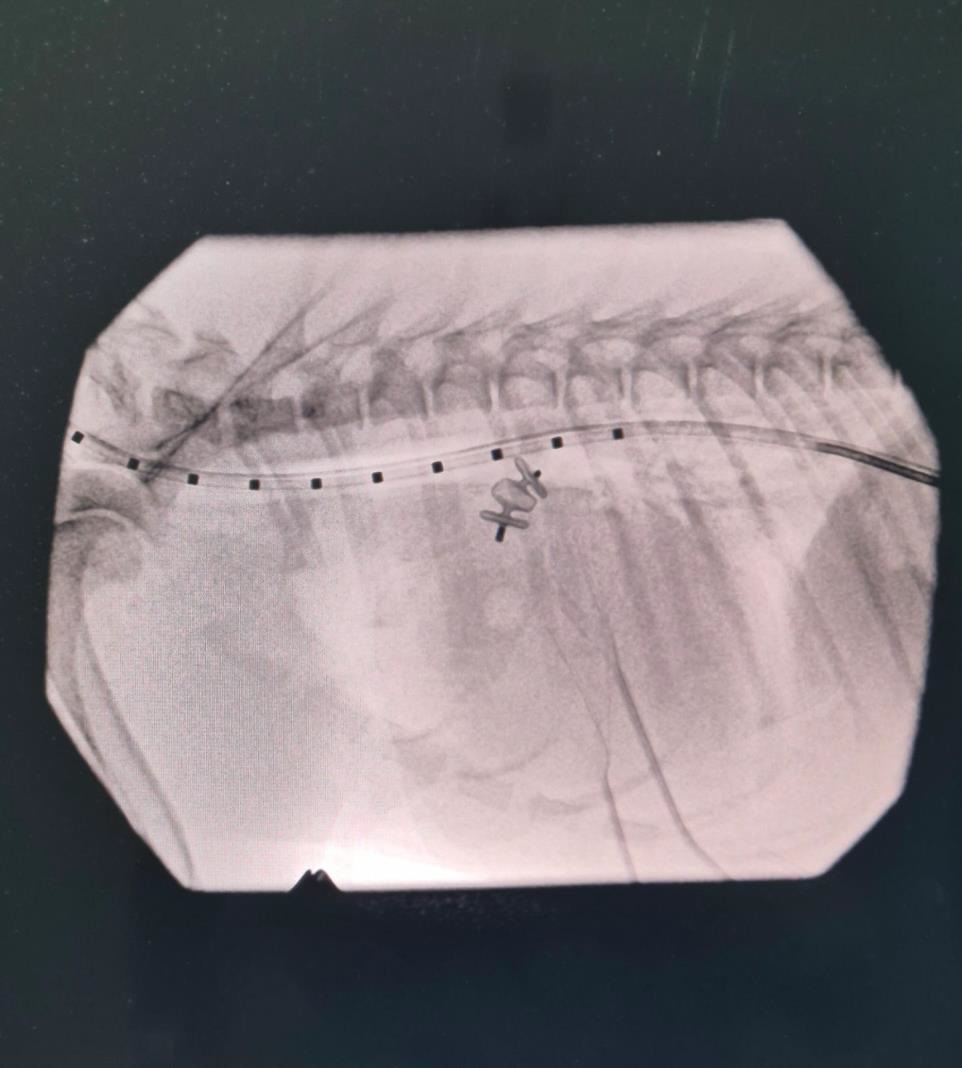

The recommended treatment was a minimally invasive PDA occlusion using interventional closure. This technique avoids open-heart surgery. A small cut is made in the skin to access a blood vessel the jugular vein. A catheter is then inserted into into the blood vessel to deliver a tiny device resembling a small umbrella to close the abnormal opening in Lily’s heart via fluoroscopy guidance.

Fluoroscopic image of the thorax, showing the occlusion of the PDA with implant at the base of the heart.